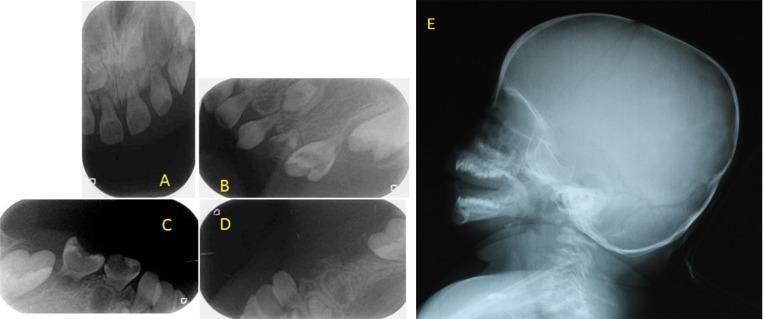

Majewski osteodysplastic primordial dwarfism type II (MOPD II) is an unusual autosomal recessive inherited form of primordial dwarfism, which is characterized by a small head diameter at birth, but which also progresses to severe microcephaly, progressive bony dysplasia, and characteristic facies and personality. This report presents a case of a five-year-old girl with MOPD II syndrome. The patient was referred to our clinic with the complaint of severe tooth pain at the left mandibular primary molar teeth. Clinical examination revealed that most of the primary teeth had been decayed and all primary teeth were hypoplastic. Patient's history revealed delayed development in the primary dentition and radiographic examination showed rootless primary molar teeth and short-rooted incisors. The treatment was not possible due to the lack of root of the left mandibular primary molars; so the teeth were extracted. Thorough and timely dental evaluation is crucial for the prevention of dental problems and the maintenance of oral health in patients with MOPD II syndrome is of utmost importance.

II型马耶夫斯基骨发育异常原发性侏儒症(MOPD II)是一种罕见的常染色体隐性遗传的原发性侏儒症,其特征是出生时头径小,但也会发展为严重的小头畸形、进行性骨发育异常以及特征性面容和性格。本报告介绍了一名患有MOPD II综合征的5岁女孩的病例。该患者因左侧下颌乳磨牙严重牙痛前来我院就诊。临床检查发现大多数乳牙已龋坏,所有乳牙均发育不全。患者病史显示乳牙列发育延迟,影像学检查显示乳磨牙无根,切牙牙根短。由于左侧下颌乳磨牙无根,无法进行治疗,因此拔除了牙齿。全面及时的牙科评估对于预防牙科问题至关重要,维护MOPD II综合征患者的口腔健康至关重要。